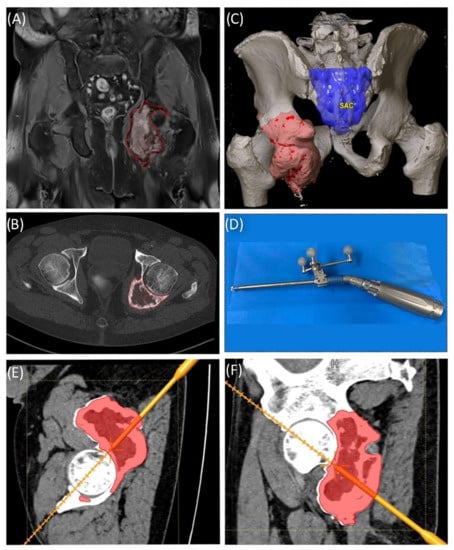

A 59-year-old female patient was diagnosed with bone metastasis of endometrial carcinoma of the sacrum with increasing and immobilizing pain. Primary radiation was discussed, but primary surgery and adjuvant radiation were preferred. Preoperatively, bladder/rectum dysfunction and a bladder-vaginal fistula were already present due to significant metastatic progression. The goal of 3D model-based planning and navigation was marginal resection of the metastasis in terms of a partial sacrectomy below S2 with ligation of the dural tube and the descending nerve roots below S2 (Figure 3 and Figure 4). Repeated revision surgery and systemic antibiotic treatment after wound infection were necessary. At the two-month follow-up, further metastases with pulmonary foci, which did not exist preoperatively, were found. Palliative treatment and radiation followed.

Figure 3. Case 2: Tumor segmentation (A) and resection plane planning (B), as well as preoperative validation of model accuracy with a navigated chisel resection of the 3D-printed model (BE).

Figure 4. Case 2: 3D model of navigated chisel resection (A); resection planes in the axial and transversal planes (C,D); intraoperative view of the navigated chisel with crosshairs showing the location of the tip (B).